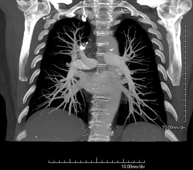

- Angio-TC Arterias pulmonares (Estudio TEP, Tromboembolismo Pulmonar) Prueba diagnóstica que consiste en el estudio de las arterias pulmonares mediante el empleo de un equipo de TC (Tomografía Computarizada) obteniendo imágenes bi y tridimensionales. En este estudio es imprescindible el uso de contraste yodado, el cual permitirá una mejor definición anatómica. Esta prueba está principalmente indicada en los casos de sospecha de tromboembolismo pulmonar (TEP) para descartar o confirmar la presencia de coágulos sanguíneos en el interior de las arterias. Prueba diagnóstica que consiste en el estudio de las arterias pulmonares mediante el empleo de un equipo de TC (Tomografía Computarizada) obteniendo imágenes bi y tridimensionales. En este estudio es imprescindible el uso de contraste yodado, el cual permitirá una mejor definición anatómica. Esta prueba está principalmente indicada en los casos de sospecha de tromboembolismo pulmonar (TEP) para descartar o confirmar la presencia de coágulos sanguíneos en el interior de las arterias.